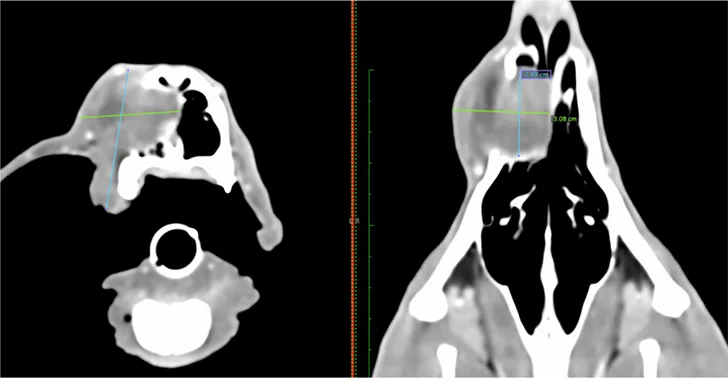

Staging tests may include dental radiography, 3-view thoracic radiography, and aspiration of the mandibular lymph nodes. A CT scan of the head and thorax is typically recommended for local and distant staging and surgical planning, especially for gingival tumors (Figure 1). For acanthomatous epulides, a CT scan of the thorax may not be necessary, as these tumors are locally aggressive but do not metastasize. Additional testing prior to surgery should include CBC, serum chemistry profile, urinalysis, and, in case blood transfusion becomes necessary, blood typing.

FIGURE 1

CT scan of a 1-year-old dog with a high-grade fibrosarcoma of the maxilla